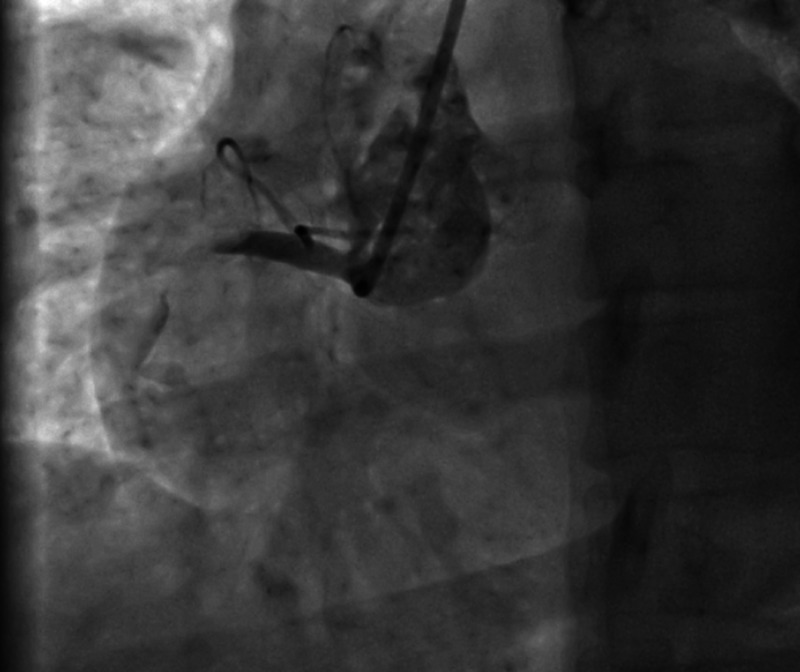

She was taken for primary percutaneous coronary intervention (PCI) and the coronary angiography, which showed a discrete eccentric 99% lesion of proximal RCA with thrombus with thrombolysis in acute myocardial infarction (TIMI) 1 flow distally. Thrombus aspiration was performed with a Thrombuster II device and the lesion was stented with 4×15 Prolink (BMS). TIMI III flow attained (door to balloon time was 45 min) (figures 1–4)

Figure 1.

Right coronary angiogram showing total block on the artery proximally.

She was taken for primary PCI and the coronary angiography showed a discrete eccentric 99% lesion of proximal RCA with thrombus with TIMI 1 flow distally. Thrombus aspiration was performed with a Thrombuster II device and the lesion was stented with 4×15 Prolink (BMS). TIMI III flow attained (DBT was 45 min) (figures 1–4)